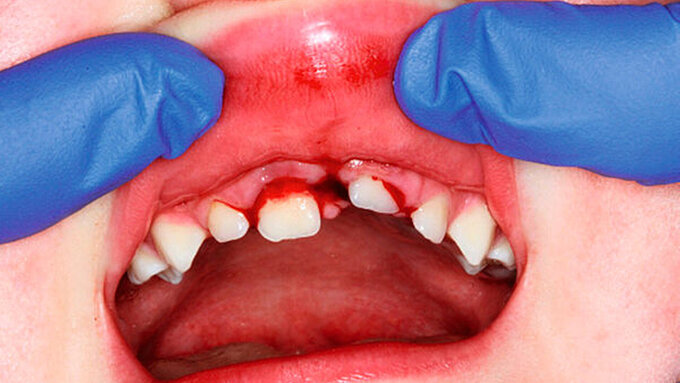

Die Schädigung der äußeren Schutzbarriere der Zahnwurzel und die gleichzeitige bakterielle Besiedlung des Wurzelkanals infolge einer Pulpanekrose führen zu externen entzündlichen Resorptionen. Diese treten häufig als Komplikation nach Zahntraumata auf, insbesondere nach Avulsionen und Intrusionen [Krastl et al., 2021; Souza et al., 2020]. Es wird berichtet, dass externe entzündliche Resorptionen vor allem bei schweren Dislokationsverletzungen entstehen [Crona-Larsson et al., 1991]. Entzündliche Resorptionen wurden bei 38 Prozent der Zähne nach Intrusionen und bei 30 Prozent der Zähne nach Replantation bei Avulsionen beschrieben [Andreasen und Pedersen, 1985; Crona-Larsson et al., 1991]. Extrusionen und laterale Dislokationen führen nur in sechs Prozent beziehungsweise drei Prozent zu entzündlichen Resorptionen. Bei leichten Verletzungen wie Konkussionen oder Lockerungen sind diese dagegen sehr selten [Andreasen und Pedersen, 1985].

Entzündliche Resorptionen sind bei fehlender klinischer Symptomatik häufig ein radiologischer Zufallsbefund. Sie können aber auch mit einer symptomatischen Entwicklung wie irreversibler Pulpitis oder apikaler Parodontitis einhergehen. Resorptionsdefekte an der Wurzeloberfläche erscheinen im Röntgenbild aufgrund ihres raschen Fortschreitens oft zerklüftet (Abbildung 6). Entlang einer unregelmäßigen Wurzelaußenkontur sind transluzente Zonen im Sinne von „schüsselförmigen“ Resorptionslakunen unterschiedlicher Größe zu erkennen. Häufig findet man verkürzte Wurzeln mit zusätzlichen periapikalen Aufhellungen. In fortgeschrittenen Fällen kann die Resorption bis ins Zahninnere vordringen und den Wurzelkanal perforieren [Andreasen und Hjørting-Hansen, 1966; Finucane und Kinirons, 2003].